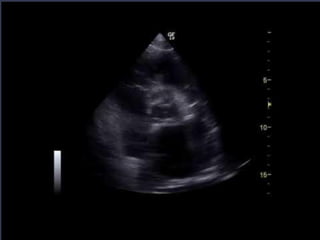

SUBCOSTAL